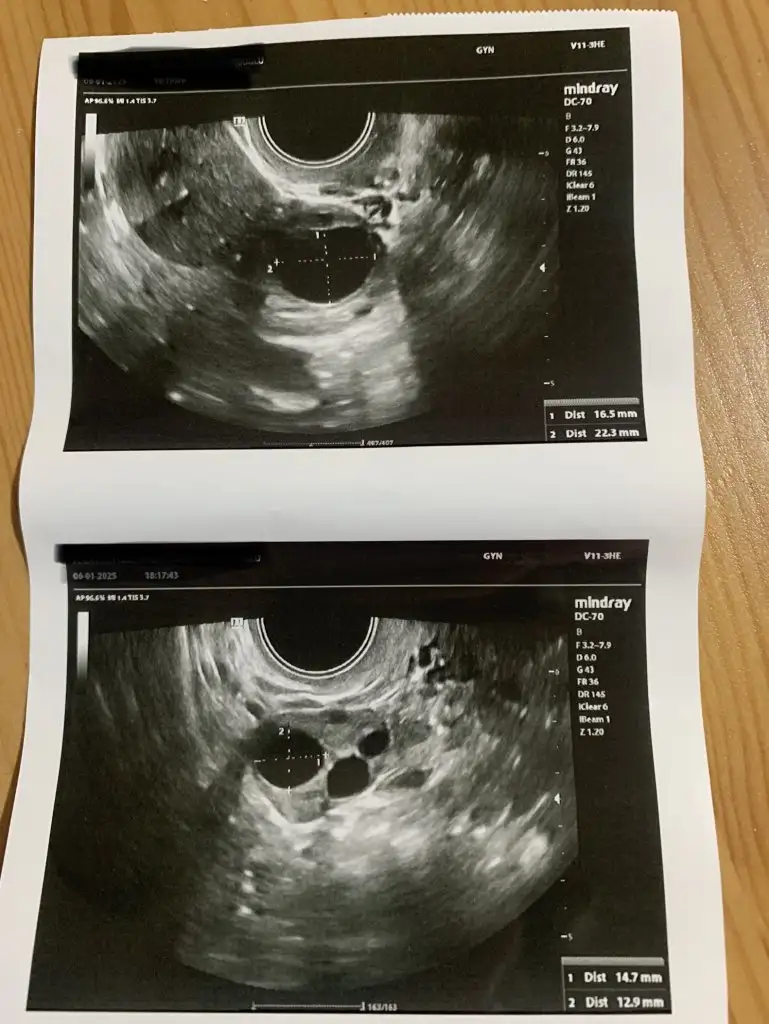

Canım bi yumurtan 16,5 diğeri de 14.7 büyümüş yani çatlama olması için daha varArkadaslar merhaba. Bu hafta 2. Asilamam olacak. Yumurta takibi icin doktordan geliyorum simdi de 2 gun sonra tekrar cagirdi kontrol icin. Catlatma ignesini en erken carsamba gece yapacagim yani. Fakat yumurta boyutlari kafami karistiriyor. Bu doktor biseyleri yanlis yapiyor gibi bi hisse kapildim. Yumurta ultrasonumu yorumlayabilecek kadar anlayan var mi aranizda? Çarşambaya kadar yumurtamin fazla buyuyecegini dusunuyorum. Eki Görüntüle 3532404

Tesekkur ederimCanım bi yumurtan 16,5 diğeri de 14.7 büyümüş yani çatlama olması için daha var

Yok canım. Ne zaman kontrole gideceksin pekiTesekkur ederim. Ben dist 2 degerlerine de bakip aritmetik ortalamayi aldim. Oyle olmuyor sanirim.